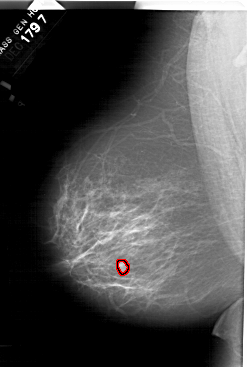

A_1518_1.LEFT_CC

LEFT_CC LINES 6871 PIXELS_PER_LINE 4126 BITS_PER_PIXEL 12 RESOLUTION 43.5 OVERLAY

FILE: A_1518_1.LEFT_CC.OVERLAY

TOTAL_ABNORMALITIES 1

ABNORMALITY 1

LESION_TYPE MASS SHAPE LOBULATED MARGINS ILL_DEFINED

ASSESSMENT 4

SUBTLETY 2

PATHOLOGY BENIGN

TOTAL_OUTLINES 1

BOUNDARY